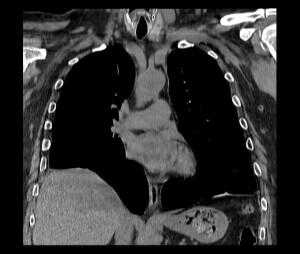

Нейрогенные парезы дыхательной мускулатуры осложняют течение ряда заболеваний центральной и периферической нервной системы. В отдельных случаях они могут быть преобладающими или единственно манифестными, вызывая диагностические трудности имитацией заболеваний дыхательной системы. Парезы диафрагмы и развившаяся на этом фоне дыхательная недостаточность могут быть следствием множества патологических процессов, включая миелит, болезни мотонейрона, полинейропатии, болезни нервно-мышечных синапсов, некоторые миопатии, герпетические полирадикулоневриты, травматические повреждения диафрагмального нерва, поражения шейного сплетения, заболевания грудной клетки и поддиафрагмальные патологические процессы [17]. Причины дисфункции диафрагмы можно классифицировать в зависимости от уровня поражения [4]. Продолговатый или спинной мозг поражается при демиелинизирующем процессе, однако парез диафрагмы довольно редко встречается при рассеянном склерозе [12, 18]. Высокое поражение спинного мозга (на уровне С1 или С2) приводит к параличу диафрагмы, в то время как при среднешейном поражении (на уровне С3-С5) функция диафрагмы частично сохраняется. Около 40% пациентов с поражением на уровне С3 нуждаются в искусственной вентиляции легких (ИВЛ), и лишь 15% пациентов с повреждением на уровне С4 или С5 [18, 33]. Заболевания верхних мотонейронов спинного мозга, как, например, боковой амиотрофический склероз или полиомиелит, часто приводят к дисфункции диафрагмы и дыхательной недостаточности. Парез диафрагмы может развиться как непосредственно сразу после инфицирования вирусом полиомиелита, так и спустя многие годы (в среднем, 35 лет) [9, 18]. К другим причинам, вызывающим парез диафрагмы и захватывающим мотонейроны спинного мозга относятся сирингомиелия, паранео-пластические моторные нейропатии и спиналь-ные мышечные атрофии. В большинстве случаев причиной осложнений и летального исхода при этих состояниях является дыхательная недостаточность [18]. Повреждение непосредственно самого диафрагмального нерва - чаще всего результат ятрогенного воздействия на него во время операции или сдавления опухолью [18, 21, 28]. В литературе описаны случаи проявления аневризмы грудного отдела аорты в форме паралича диафрагмального нерва. Симптомы также включали дисфонию, хроническую боль в груди и прогрессирующую дисфагию [5, 24]. К другим состояниям, способным вызвать непосредственное поражение диафрагмального нерва можно отнести травмы, инфекционные поражения (герпетическая инфекция, болезнь Лайма) и воспалительные процессы. Синдром Гийена-Барре часто осложняется вовлечением диафрагмального нерва [18, 31]. Так, от 20% до 30% госпитализированных пациентов с установленным диагнозом синдрома Гийена-Барре нуждаются в эндотрахеальной искусственной вентиляции легких [15]. Согласно данным исследования в Англии 25% и 23% [15] больным синдромом Гийена-Барре необходима ИВЛ [6]. Известно, что приблизительно у 5% пациентов с невралгической амиотрофией (синдромом Пэрсонейдж-Тёрнера) имеется вовлечение диафрагмального нерва [18, 29]. Болезни с нарушением синаптической передачи могут манифестировать с дисфункции диафрагмы. Острая дыхательная недостаточность часто возникает при миастеническом кризе, что приводит к необходимости искусственной вентиляции легких. Реже дисфункция диафрагмы встречается при синдроме Ламберта-Итона, ботулизме, наследственных и приобретенных миопатиях, а также при отравлении аминогликозидами, фосфорорганическими веществами [18]. Важно помнить о вероятности развития атрофии диафрагмы, которая может возникнуть даже после короткого периода искусственной вентиляции легких. Она связана с атрофией как быстро, так и медленно сокращающихся мышечных волокон. Так, недостаточное питание или такие метаболические сдвиги, как гипофосфатемия, гипомагниемия, гипокалиемия, гипокальциемия могут способствовать дисфункции диафрагмы и продлевать потребность в искусственной вентиляции [14, 18, 19]. Среди пациентов с диспноэ, ортопноэ или гиперкапнической дыхательной недостаточностью неуточненной этиологии следует учитывать возможность наличия нейропатии диафрагмального нерва (НДН) [30]. В современной литературе она часто описывается в сочетании с болью в шее и плече, часто возникающей после инфекционных заболеваний или операций, что позволило считать НДН возможной состовляющей невралгической амиотрофии плечевого пояса (синдрома Персонейджа-Тернера). Идиопатическая НДН, вероятно, является отдельной нозологической формой в спектре иммуноопосредованных фокальных нейропатий, и, напротив, не ассоциирована с такими симптомами как боли в плече, шее, парезом верхней конечности [16, 17, 20, 23, 29, 30, 32]. Различают одностороннюю и двустороннюю НДН. Односторонняя НДН зачастую не приводит к значимым дыхательным нарушениям и протекает клинически бессимптомно, что объясняет ее гиподиагностику и, как следствие, малую распространенность описаний в литературе [16, 23]. Интерес представляет клиническое наблюдение НДН, сделанное в нашей клинике. Больной К., 39 лет, поступил в приемное отделение Республиканской клинической больницы 09.04.2015 г. с жалобами на выраженную одышку экспираторного характера в покое, сухой непродуктивный кашель, повышение температуры до 37,6˚С. Заболел около 3 недель назад, когда на фоне полного здоровья появилась одышка в покое, усиливающаяся при физической нагрузке, надевании специализированной формы (больной работает пожарным). Одышка продолжалась на протяжении около 2 недель, затем присоединилось повышение температуры до 37,5˚С, кашель. Отмечает, что за неделю до начала заболевания появились ноющие боли в плече, не связанные с движением, продолжались 2 дня, затем появились ноющие боли в шее, которые купировались внутримышечным введением диклофенака в течение 3 дней. У пациента из сопутствующих заболеваний в анамнезе вирусный гепатит С, минимальной степени активности, по поводу чего один год назад получал лечение интерфероном. Пациент не злоупотребляет алкоголем, курил с 16-летнего возраста в течение 23 лет по 1-2 пачки сигарет в день, бросил курить в ноябре 2014 года. Наследственный анамнез не отягощен. При поступлении общее состояние тяжелое ввиду диспноэ. Температура тела 37,6˚С. Телосложение правильное, питание достаточное, костно-мышечная система без особенностей. Кожа и видимые слизистые физиологической окраски, теплые, нормальной влажности. Дыхание жестковатое, ослаблено в нижних отделах, хрипов нет, ЧДД 19 в минуту. Сатурация кислорода 93% без подачи кислорода. Тоны сердца приглушены, ритмичные, АД 160/100 мм рт. ст., ЧСС 89 в минуту. Живот мягкий, безболезненный, на вдохе западение передней брюшной стенки. Периферических отеков нет. В неврологичес- ком статусе: сознание ясное, поведение адекватное, команды выполняет. ЧМН: без особенностей. Объем активных и пассивных движений конечностей полный. Мышечная сила достаточная по всем группам. Сухожильные рефлексы с верхних и нижних конечностей равные, живые. Поверхностная, глубокая чувствительность не изменена. Координаторные пробы выполняет удовлетворительно, в пробе Ромберга устойчив. Менингеальных знаков нет. Функции органов таза не нарушены. Пациент был переведен в отделение реанимации и интенсивной терапии и подключен к аппарату “Dager Savina” в режиме BIPAP для проведения неинвазивной масочной ИВЛ. Проведены обследования: ИФА на гепатит С от 10.04.2015 положительный, RW, HBsAg, ВИЧ от 10.04.2015 отрицательно. ОАК от 09.04.2015: лейкоциты 10,0*109/л, эритроциты 4,77*1012/л, гемоглобин 144 г/л, гематокрит 41,5%, тромбоциты 287000. ОАМ от 10.04.2015: цвет соломенно-желтый; прозрачная; удельный вес 1015; белок - отрицательно; лейкоциты единичные в поле зрения; эритроциты 1-2 в поле зрения; бактерии +. БАК от 09.04.2015: калий 4,3 ммоль/л, натрий 136 ммоль/л, общий белок 67,5 г/л, мочевина 7,3 ммоль/л, креатинин 80 мкмоль/л, АЛТ 29 ед/л, АСТ 15 ед/л, КФК 137 ед/л, ЛДГ 118 ед/л, общий билирубин 4,4 ммоль/л, холестерин 4,32 ммоль/л. Коагулограмма от 09.04.2015: ПТИ 98%, фибриноген 4,3 г/л, АЧТВ 27 сек. ЭКГ от 09.04.2015: синусовый ритм с ЧСС 67 в мин., нормальное положение ЭОС (+41˚), RV5>V6>RV4. Рентгенограмма ОГК от 10.04.2015: легочная ткань воздушна. Легочный рисунок диффузно обогащен за счет перибронхиальных и периваскулярных уплотнений, интерстициальной сетчатости, сгущен в нижних отделах легких. Корни с не совсем четкой структурой, полнокровны. Высокое стояние диафрагмы. Костодиафрагмальные синусы свободны, тень сердца без особенностей (рис. 1). Спирометрия от 02.04.2015: ОФВ1 1,88л, ЖЕЛ 2,07 л, ФЖЕЛ 2,33 л, ОФВ1/ФЖЕЛ 81%, рестрикция средне-тяжелой степени, возможно умеренные обструктивные нарушения; после пробы с бронхолитиком без динамики (ОФВ1/ФЖЕЛ 80%). УЗИ плевральных полостей от 12.04.2015: в правой плевральной полости жидкость не визуализируется; в левой плевральной полости жидкость не визуализируется. РКТ легких от 02.04.2015: РКТ признаки компрессионных ателектазов обоих легких, релаксации обоих куполов диафрагмы (рис.2). Стимуля-ционная ЭМГ от 20.04.2015: латентность М-ответа при стимуляции диафрагмального нерва справа составила 6,2 мс, слева 6,3 мс (при норме от 6 до 9 мс); амплитуда М-ответа при стимуляции диафрагмального нерва справа составила 0,5 мкВ, слева 0,4 мкВ (при норме от 3,5 до 7,4 мкВ). Кино-МРТ от 20.04.2015: отме- чается двухстороннее отсутствие дыхательной экскурсии центральных и задних отделов диафрагмы с наличием слабой пассивной дыхательной экскурсии передних отделов диафрагмы, осуществляемой за счет движений передней брюшной стенки; МРТ-признаки двустороннего паралича диафрагмы. Таким образом, пациенту был выставлен диагноз: Двусторонний полисегментарный ателектаз-аневмония на фоне паралича куполов диафрагмы, обусловленного двусторонней идиопатической нейропатией диафрагмального нерва. Пациент получал лечение: неинвазивная масочная ИВЛ, 2,4% раствор эуфиллина 10,0 в/в капельно на 250,0 0,9% раствора натрия хлорида, клексан 0,4 мл п/к, ацетилцистеин 9,0 в/в, цефотаксим 1 г на 10,0 0,9% раствора натрия хлорида в/м №10. На фоне проведенной терапии состояние пациента нормализовалось, однако сохранялась одышка при физической нагрузке. При динамическом наблюдении до настоящего момента у пациента сохраняются жалобы на одышку при быстрой ходьбе, физической нагрузке, после еды и в положении лежа, объективно сохраняется парадоксальное дыхание. Ниже представлены основные выводы, полученные в результате анализа литературы, посвященной проблеме нейропатии ДН. S. Podnar (2015) выделил критерии диагноза НДН: 1) амплитуда М-ответа

КТ. Наиболее информативным методом исследования является компьютерная томография, дающая полную информацию о степени релаксации и характере изменений органов грудной и брюшной полостей. Во всех случаях релаксации, даже при небольшой ее выраженности, наблюдается ателектаз и воспалительные изменения базальных сегментов легкого. С внедрением компьютерной томографии практически отпала надобность в остальных традиционных методах дифференциальной диагностики.

Релаксация правого купола диафрагмы на КТ